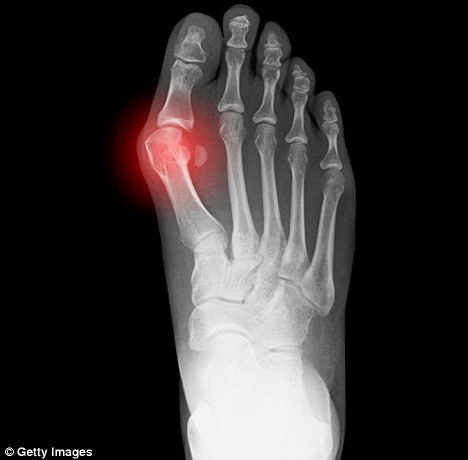

Gout is caused by too much uric acid in the blood (hyperuricemia) and in the tissues. At a certain point, uric acid forms crystals in the joints which the immune system attacks causing redness, swelling, warm and painful joints. The big toe is especially affected by gout and the slightest touch of the hot toe can elicit intense pain. Other joints can be involved and this condition can become chronic.

Gouty arthritis attacks come on suddenly and frequently at night. Alcohol excess and changes in urate sensitive medications are two reasons that precipitate the attacks. As noted, an attack

causes red, swollen, warm painful joints. The big toe is the most susceptible joint (‘podagra’) and the pain becomes more intense as the attack progresses.